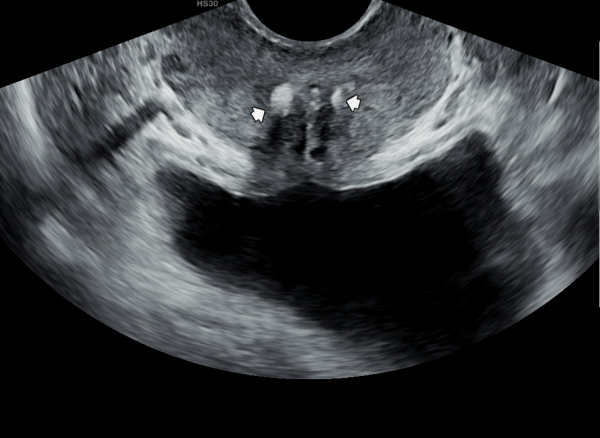

수년전 부터 하복부 통증과 사정시 혈정액을 주소로 여러 비뇨기과와 상급병원에서 치료를 했으나 증상의 호전이 없다고 내원당일 검사한 경직장 전립선 초음파 검사상 사정관 입구에 결석과 사정관의 낭종이 관찰되는 초음파 사진입니다.

The transrectal prostate ultrasound image taken on the day of the patient's first visit shows a stone at the ejaculatory duct opening and a cyst in the ejaculatory duct.

The patient had been experiencing lower abdominal pain and hematospermia during ejaculation for several years, and had received treatment at multiple urology clinics and advanced hospitals without symptom improvement.

첫 내원 당일 정면 경직장 전립선 초음파 사진상 좌우 사정관 입구에 결설이 관찰되고 전립선의 결절이 관찰되는 초음파 사진입니다.

This is a frontal transrectal prostate ultrasound image taken on the patient's first visit, showing calculi (stones) at the openings of both ejaculatory ducts and nodules within the prostate.![]()